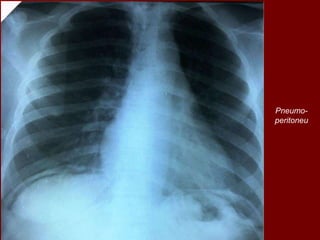

Pneumo-

peritoneu

Pneumoperitoneu